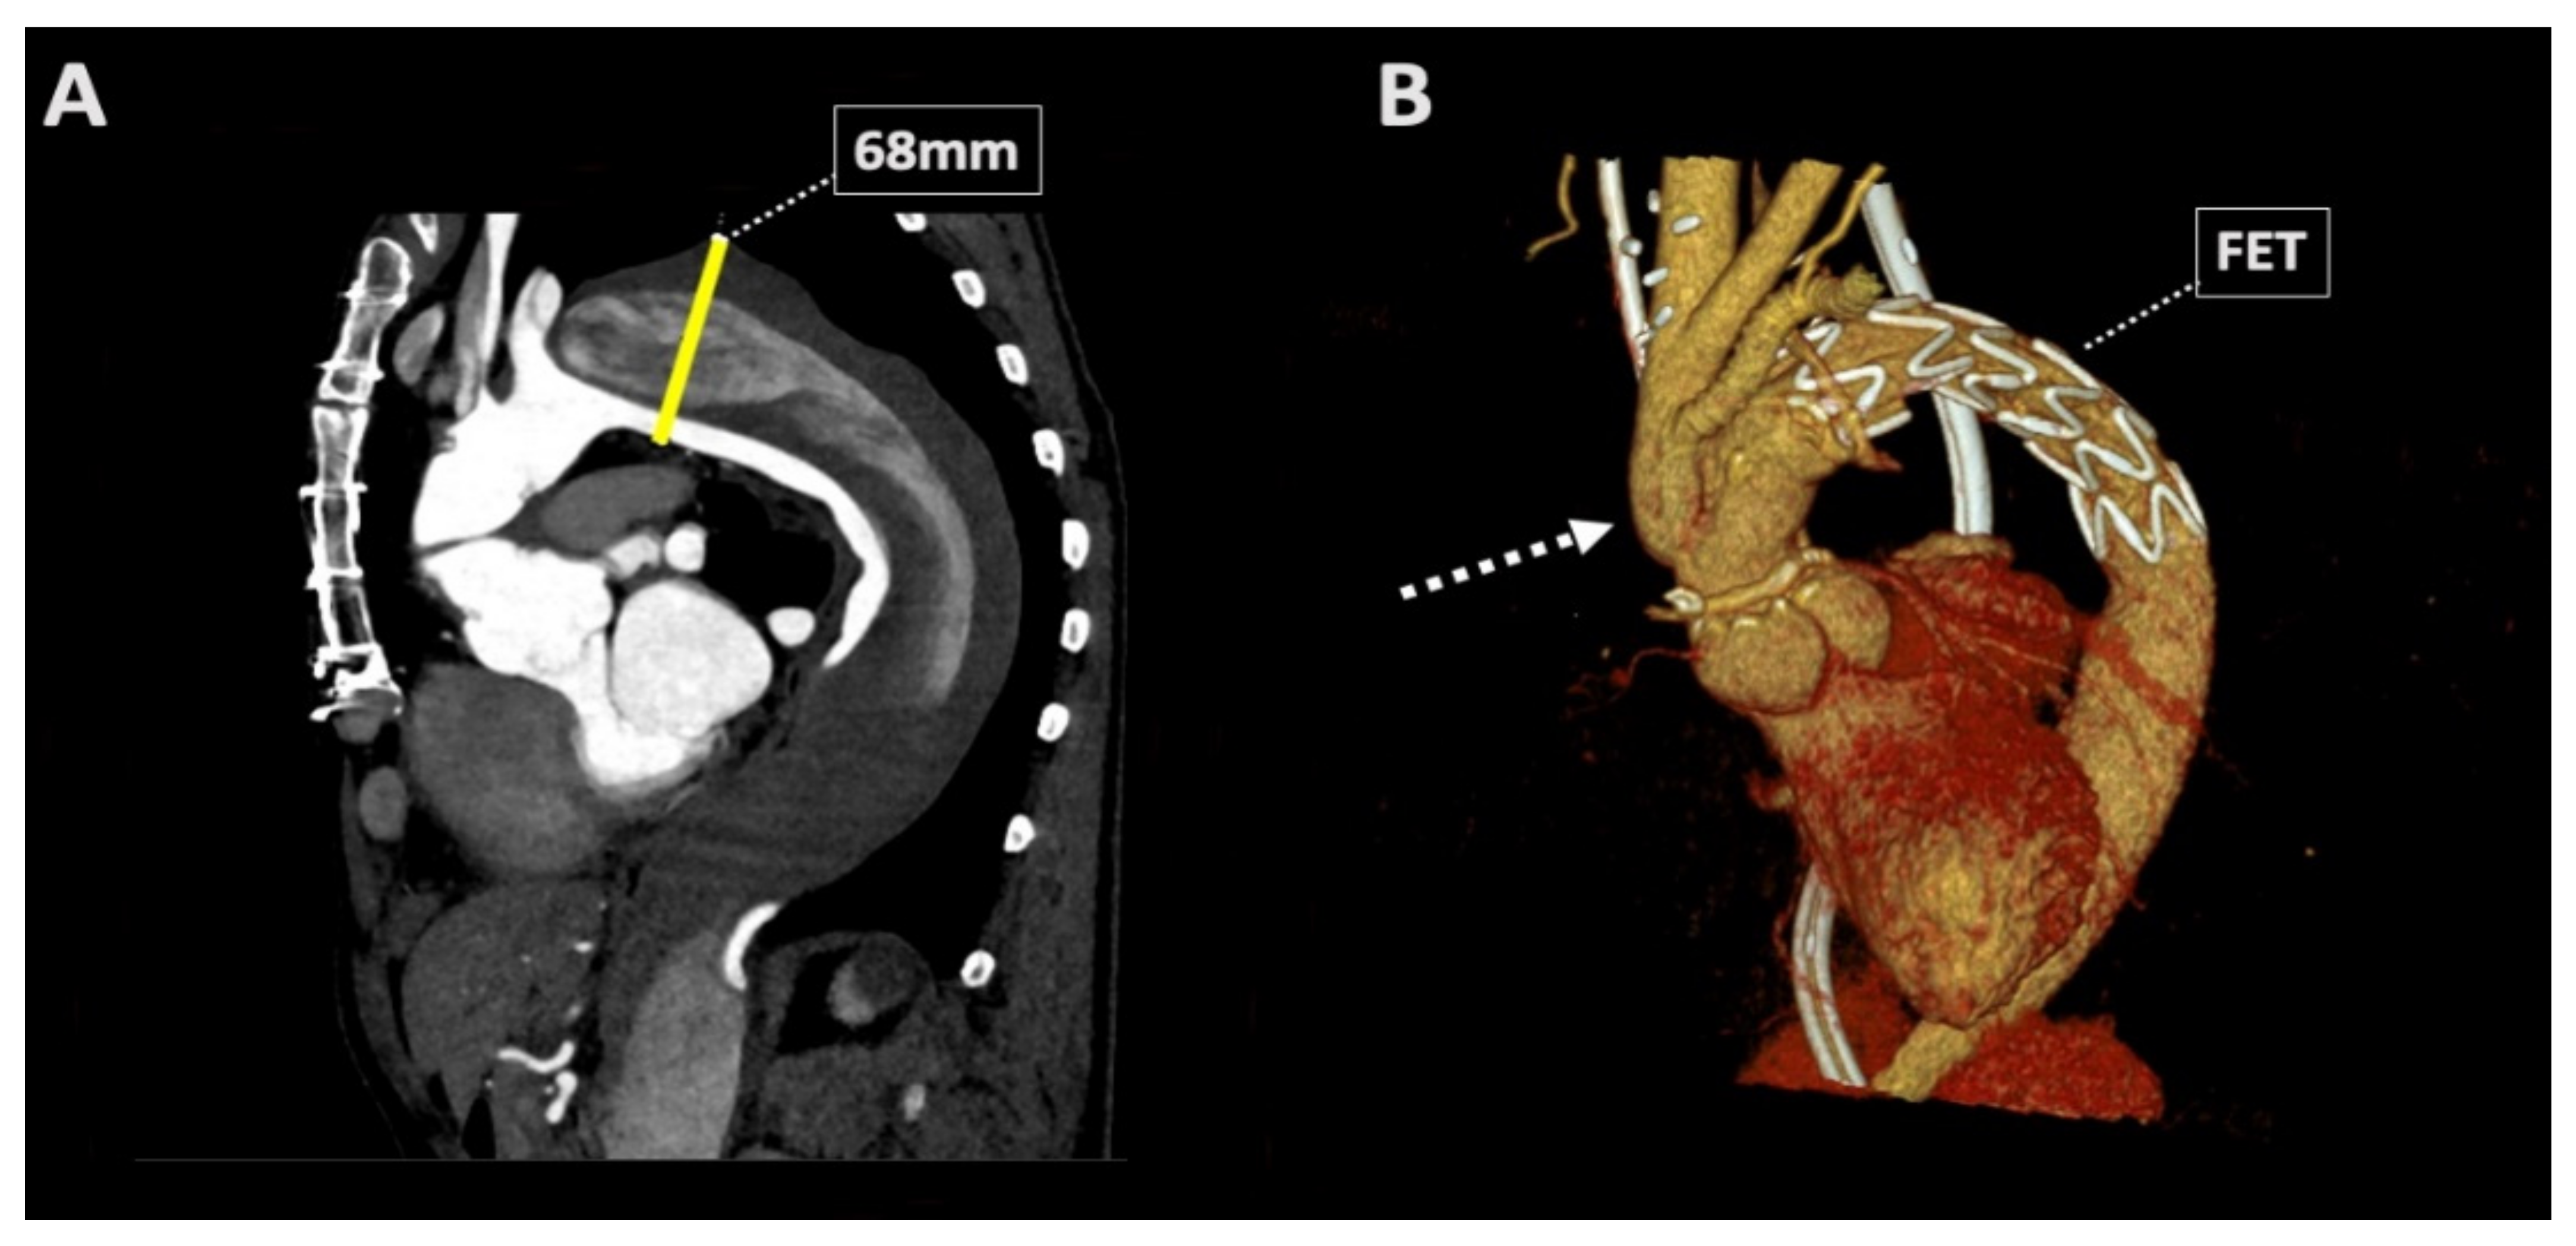

2. Case Report